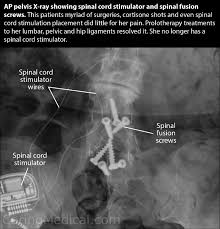

Even though the doctor monitors or evaluates you continuously to avoid dependency of opioids. Post Laminectomy Syndrome Treatment for Pain After Back Surgery in Texas Spine surgeons perform back surgery to reduce or eliminate chronic back or leg pain due to spinal nerve compression. For chronic post laminectomy pain we may recommend spinal cord stimulation.

For chronic post laminectomy pain we may recommend spinal cord stimulation.

For muscle spasm we may recommend trigger point injections into the muscles. An experienced spinal pain specialist can examine your condition and help you explore your treatment options. If you have had back surgery that failed to relieve the pain then you may be suffering from post-laminectomy syndrome. An epidural adhesiolysis removal of scar tissue that has formed because of the surgery that surrounds the spinal nerves is considered an effective treatment option for lumbar Post-laminectomy syndrome. Should surgery fail to achieve all of its desired outcomes the result is known as Post-Laminectomy Syndrome sometimes called Failed Back Syndrome. At this time there are no studies that evaluate the use of regenerative medicine on post laminectomy pain patients. For chronic post laminectomy pain we may recommend spinal cord stimulation.